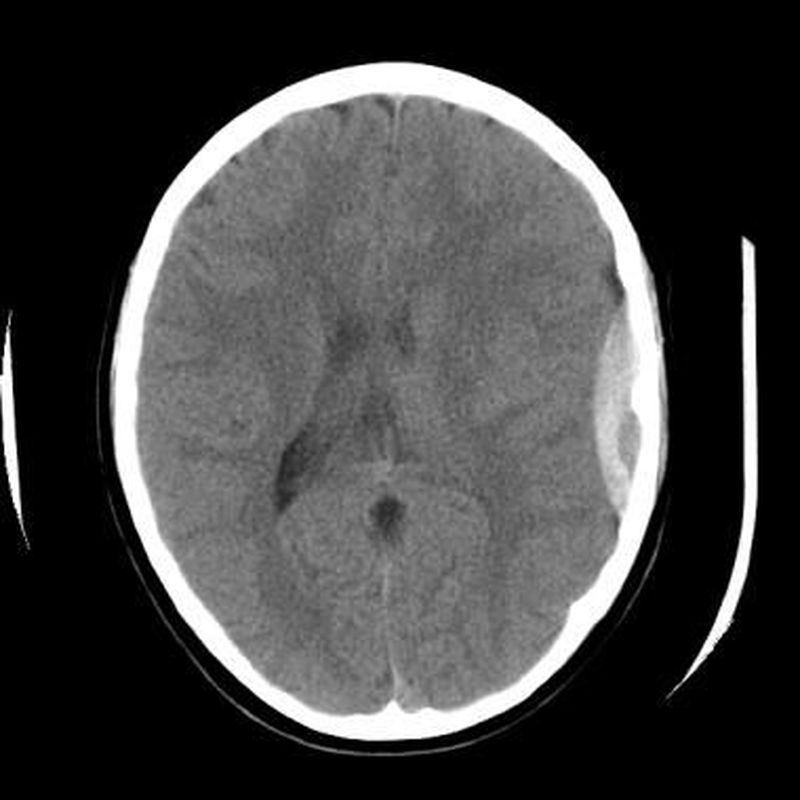

What's your diagnosis?!

1.subdural hematoma 2.epidural hematoma

Epidural hematoma.... Cresent shape and not cross skull suture it happen mainly from middle maningeal artery